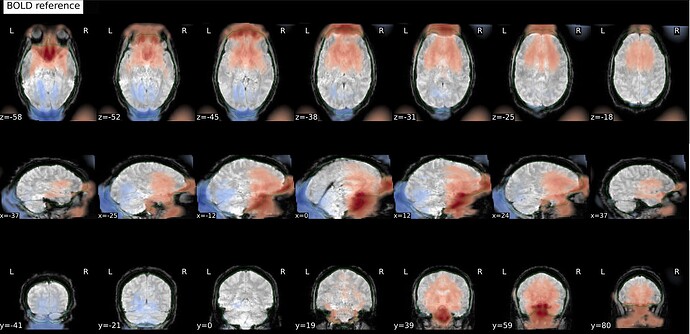

Hi everyone! I’m currently trying to use fMRIPrep to preprocess a dataset from openneuro (ds006072). fMRIPrep is running smoothly in general, but there seems to be a problem with SDC, which leads to a distorted and elongated corrected image. This is one example, but the data for all my sessions is similarly distorted:

This is what the distorted version looks like, before SDC: